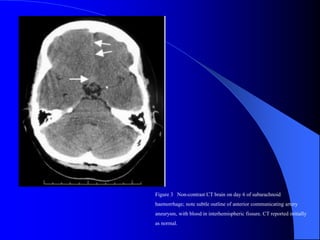

Figure 3 Non-contrast CT brain on day 6 of subarachnoid

haemorrhage; note subtle outline of anterior communicating artery

aneurysm, with blood in interhemispheric fissure. CT reported initially

as normal.

 Mujer de 42 años con antecedentes de migraña,

sufre un dolor de cabeza súbito antes de comenzar

una clase de gimnasia, con vómitos y fotofobia.

Un medico le dg migraña y le indica morfina. Pasa

los siguientes 4 días en cama con la peor cefalea

de su vida. Otro medico reconoce la gravedad de

los smas y la estudia. No poseía alteraciones al

examen físico. Le realizan TAC que es informada

primero como normal y luego en retrospectiva un

neurorradiólogo informa hsa de comunicante

anterior. Se le realizó PL que mostró 4000

eritrocitos en 3 frascos sucesivos. Se confirmó la

HSA y la angiografía mostro aneurisma que fue

clipado. Se fue de alta sin alteración neurológica.

Conclusiones del caso

 El síntoma inicial de la pte fue mal

interpretado: una cefalea de comienzo

brusco incluso en un migrañoso, es una

HSA antes de que se pruebe lo contrario

 Un examen físico normal y una TAC

normal no excluye una HSA

 Una tomografía informada por un no

especialista tampoco excluye

 El que posee una cefalea 1° también puede

sufrir una cefalea 2°!